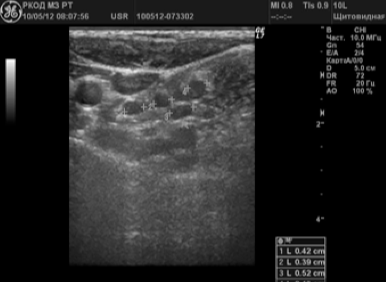

В 58 (38,2%) случаях было заподозрено метастатическое поражение лимфатических узлов. Измененные ЛУ имели размеры от 6 до 65 мм; 72,4% лимфатических узлов имели шарообразную форму, П/ПЗ2,0; 17,3% — неправильную форму в виде конгломератов. У 24 (41,4%) пациентов были выявлены единичные измененные лимфоузлы; у 34 (58,6%) — множественные. У 79,3% лимфоузлов отсутствовала дифференциация на кору и ворота; у 20,7% — ворота определялись в виде мелкого гиперэхогенного включения. 70,8% лимфатических узлов были гипоэхогенными (рис. 3); 12% — анэхогенными; 17,2% — неоднородную структуру с участками повышенной и пониженной эхогенности, с жидкостными включениями и кальцинатами (рис. 4).

Рисунок 3.

Метастазы в лимфоузлы шеи при раке щитовидной железы

Вторичное поражение (метастазы) лимфатических узлов характеризуется изменением формы на округлую с размытыми контурами (рис. 3). В МКНЦ имени А.С. Логинова можно своевременно пройти исследование лимфатических узлов в отделении ультразвуковой диагностики. Осмотр проводится на аппаратах экспертного класса. Проведение УЗИ на данных аппаратах позволяет: